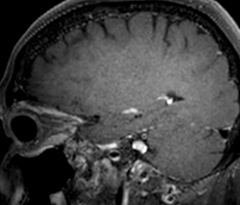

Improving scan time and/or spatial resolution

A two year follow-up scan of a CPA meningioma using both Ingenia 3.0T without CS and Ingenia Elition 3.0T with Compressed SENSE allows for a nice comparison to demonstrate the protocol improvements achieved on the Elition: 3D FLAIR has a shortened scan time, improved SNR and still the same spatial resolution. BrainView (3D T1 TSE) has improved spatial resolution and SNR with shortened scan time. For 3D T2 Drive the spatial resolution has been improved. 3D THRIVE used to have an interpolated 0.8 mm slice thickness, but true thickness at 1.6 mm, so that axial slices displayed a decent quality, but reformats were suboptimal. Compressed SENSE is used on Elition to improve spatial resolution and reduce the non-interpolated slice thickness to allow smoothly reformatted images. Total scan time (adding SmartBrain and an additional b2000 diffusion) was 13:19 on Ingenia, and is now reduced to 10:42 on Ingenia Elition.

Ingenia Elition 3.0T with Compressed SENSE

3D FLAIR 1.0 x 1.0 x 1.0 mm* 2:50 min.

3D TSE T1w 1.0 x 1.0 x 1.0 mm* 2:10 min.

3D T2w Drive 0.7 x 0.7 x 0.7 mm* 2:52 min.

3D T1w THRIVE 0.7 x 0.7 x 0.8 mm* 1:30 min.

*true voxel size, without interpolation